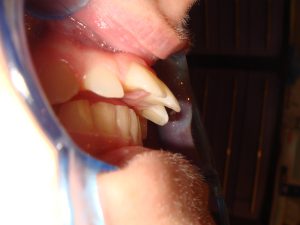

Teeth can be repeatedly filled when broken, with bigger and...

Read More +Replacing failing teeth